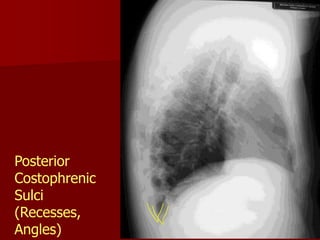

Posterior

Costophrenic

Sulci

(Recesses,

Angles)